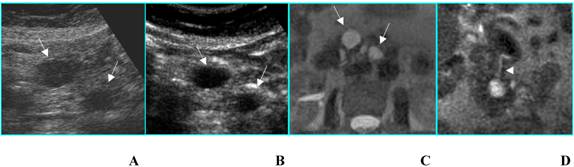

Adenocarcinoma in a 85-year-old woman who presented with diabetes at sudden onset. A. B-mode US (transverse scan) shows a hypoechoic mass, located in the head of the pancreas (asterisks), 3.5 cm in diameter. Splenic vein (arrow) is visible. B. On CEUS the mass is hypoechoic (asterisks) compared to the surrounding parenchyma in the arterial phase. C. MDCT curved reformatted image depicts pancreatic duct dilatation and hypodense lesion in the head of the pancreas.

Int J Med Sci Image

a) Ductal adenocarcinoma is usually hypoechoic (absent or poor enhancement compared to normal pancreatic parenchyma), because of its scanty vascularization [2] (Fig. 1). In particular, tumors in which the size of the hypoechoic area is unchanged on CEUS have clear margins with no infiltration or inflammation; tumors in which the size of the hypoechoic area is reduced on CEUS have blurred margins with infiltration of cancerous cells and inflammation. CEUS may be a tool for evaluating pathologic changes of pancreatic cancer and may provide useful information in the pre-treatment phase [2].

Ductal adenocarcinoma is rarely isoechoic (enhancement similar to normal pancreatic parenchyma); this pattern is due to a moderate vascularization (Fig. 2) occurring in some histotypes (anaplastic carcinoma and acinar cell carcinoma) [3]. The isoechoic pattern is often observed in focal pancreatitis too [4]: therefore, CEUS is not always able to accurately differentiate adenocarcinoma from focal pancreatitis, as well as CT and MR [5].